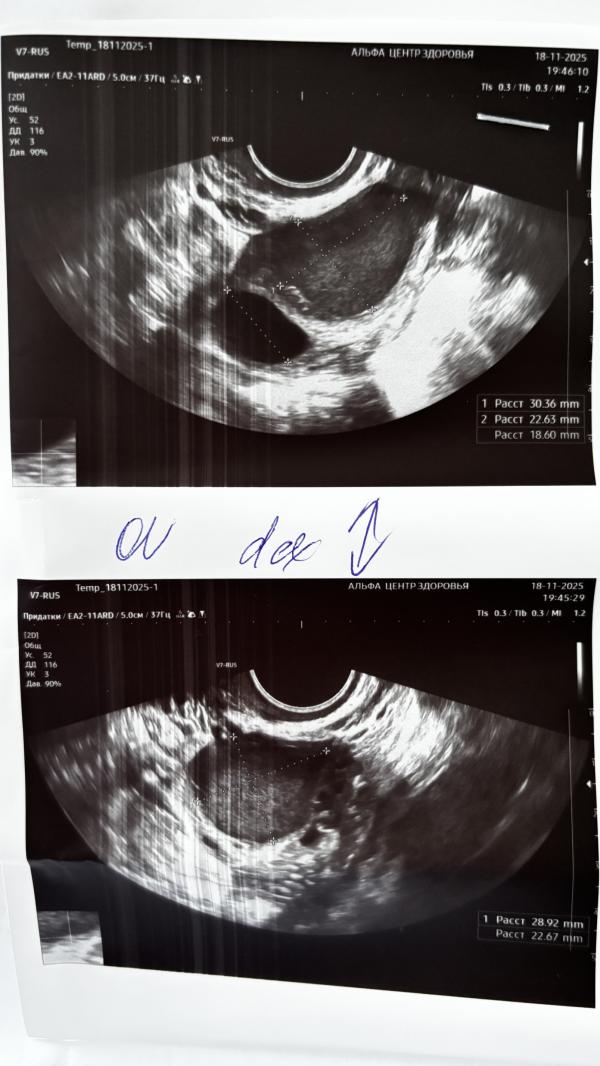

В понедельник прихватило живот, да так что я пошевелиться не могла, боль была как перед кд, но сильнее намного. Через 1,5 ч. отпустило. Вчера на узи на яичнике нашли кисту эндометриоидную (эндометриому), сказали повторить узи в начале следующего цикла, и если она не уйдет, то оперировать😭😭😭, а пока назначили свечи дикловит на 10 дней.